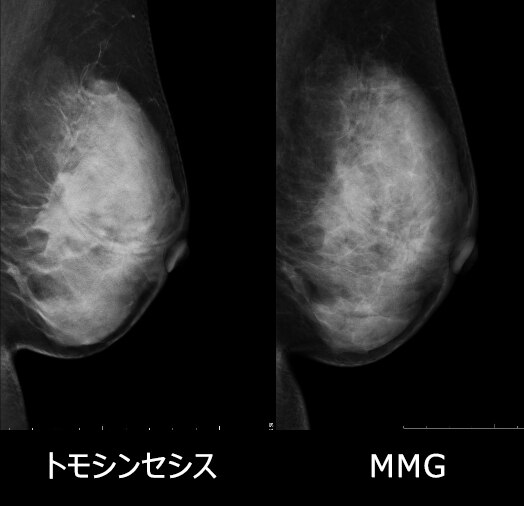

• MMG所見:右乳房M/O域 FAD+、淡く不明瞭な石灰化が集簇性にあり、カテゴリー3

• トモシンセシス:16.5㎜大の分葉形等~高濃度腫瘤あり、境界は微細鋸歯状、構築の乱れを伴い、淡く不明瞭な石灰化伴う→存在診断がより明確になりカテゴリー4にあがる症例

• 病理組織:Invasive ductal carcinoma scirrhous type